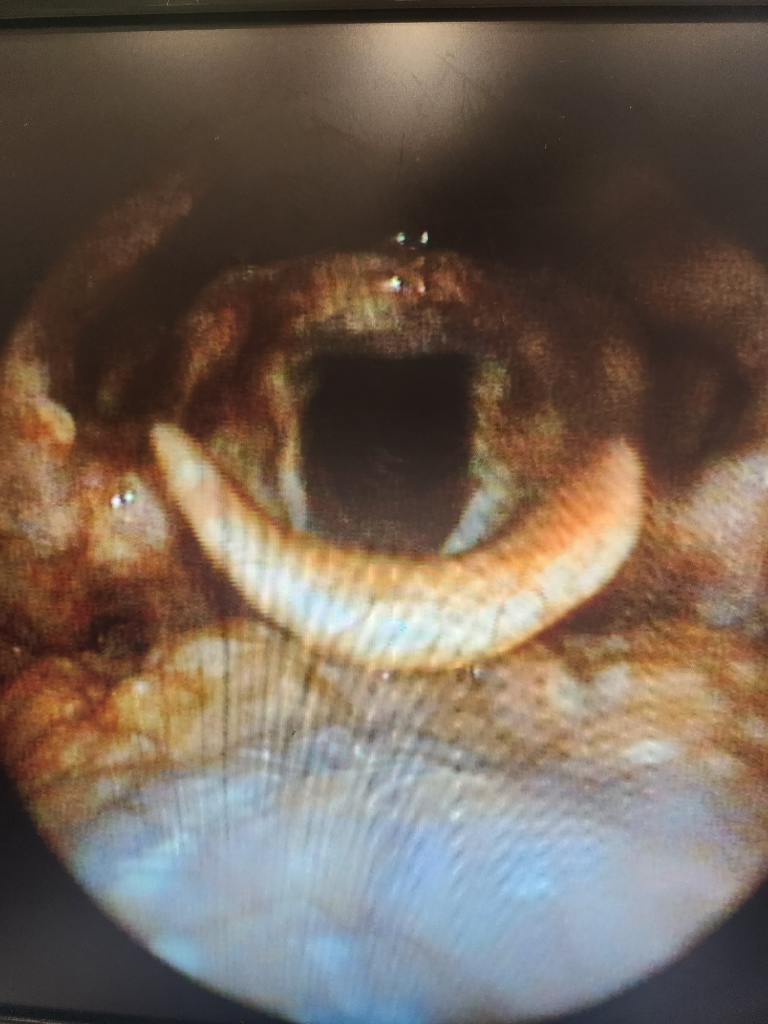

1,2일차에는 고열, 오한으로 39도넘게 열이났었고

4일차인데 후두쪽으로 염증이 더 퍼진거같아요

음식섭취도 불가하고 목 작열감에 잠도깹니다ㅠㅜ

대학병원 진료하고 입원을 할수있을까요?

인후두염의 경우 대학병원에 입원할 정도의 상태는 아니랍니다. 먹는 항생제를 복용하면서 증상 조절을 해 볼 수 도 있을 것이구요. 입원을 원하신다면 준종합병원에 문의하셔야 될 것 같습니다.

입원 판단 여부는 진료의의 판단에 따라서 결정되기 때문에 해당 정보만 보고 구체적으로 가능하다 가능하지 않다 판단해드릴 수는 없습니다.